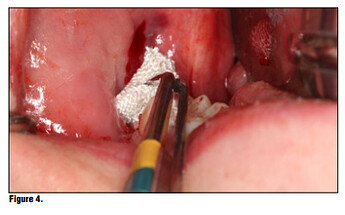

Bioviva is individually packaged. (Figure 1). The product is packed in individual blister packs in 1.9 cm squares for ease of use and to avoid any cross contamination issues (Figure 2). Simply puncture the packaging backing and remove the gauze from the packaging using dry forceps to avoid the gauze from sticking to the forceps (Figure 3). The product can be cut to size if the gauze is larger than the site, or the product can be folded to properly fit using tissue forceps (Figure 4).